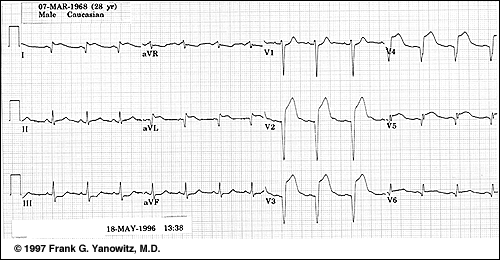

TULBURARI DE RITM SI DE CONDUCERE

TULBURARI DE RITM SI DE CONDUCERE 1. Flutterul atrial Este o disritmie produsa prin depolarizari atriale regulate, rapide, cu o frecventa de 250-350/min Apare un BAV care face ca numai o parte din impulsurile atrialeCiteste tot ... 518 cuvinte

Dimensiune mica

+ cu imagini |

INFARCTUL MIOCARDIC: ISCHEMIE, LEZIUNE, NECROZA

INFARCTUL MIOCARDIC: ISCHEMIE, LEZIUNE, NECROZA Cardiopatia ischemica (CI) Este cauzata de anoxie, secundara insuficientei coronariene acute sau cronice (tahicardie, hemoragie, soc cu prabusire tensionala, intoxicatii cu COCiteste tot ... 1197 cuvinte

Dimensiune mica

+ cu imagini |